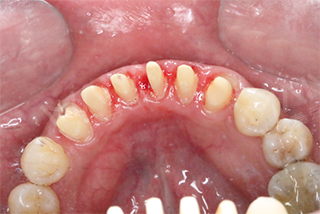

1、将牙龈作激光环切处理,同时上下颚的烤瓷牙做拆冠制作,按照色标的参数值,初步检查咬合接触关系。

2、充分运用仿生学美学修复技术,患者修复后的咬合关系和整体美观与协调性反复的进行数字化模拟。